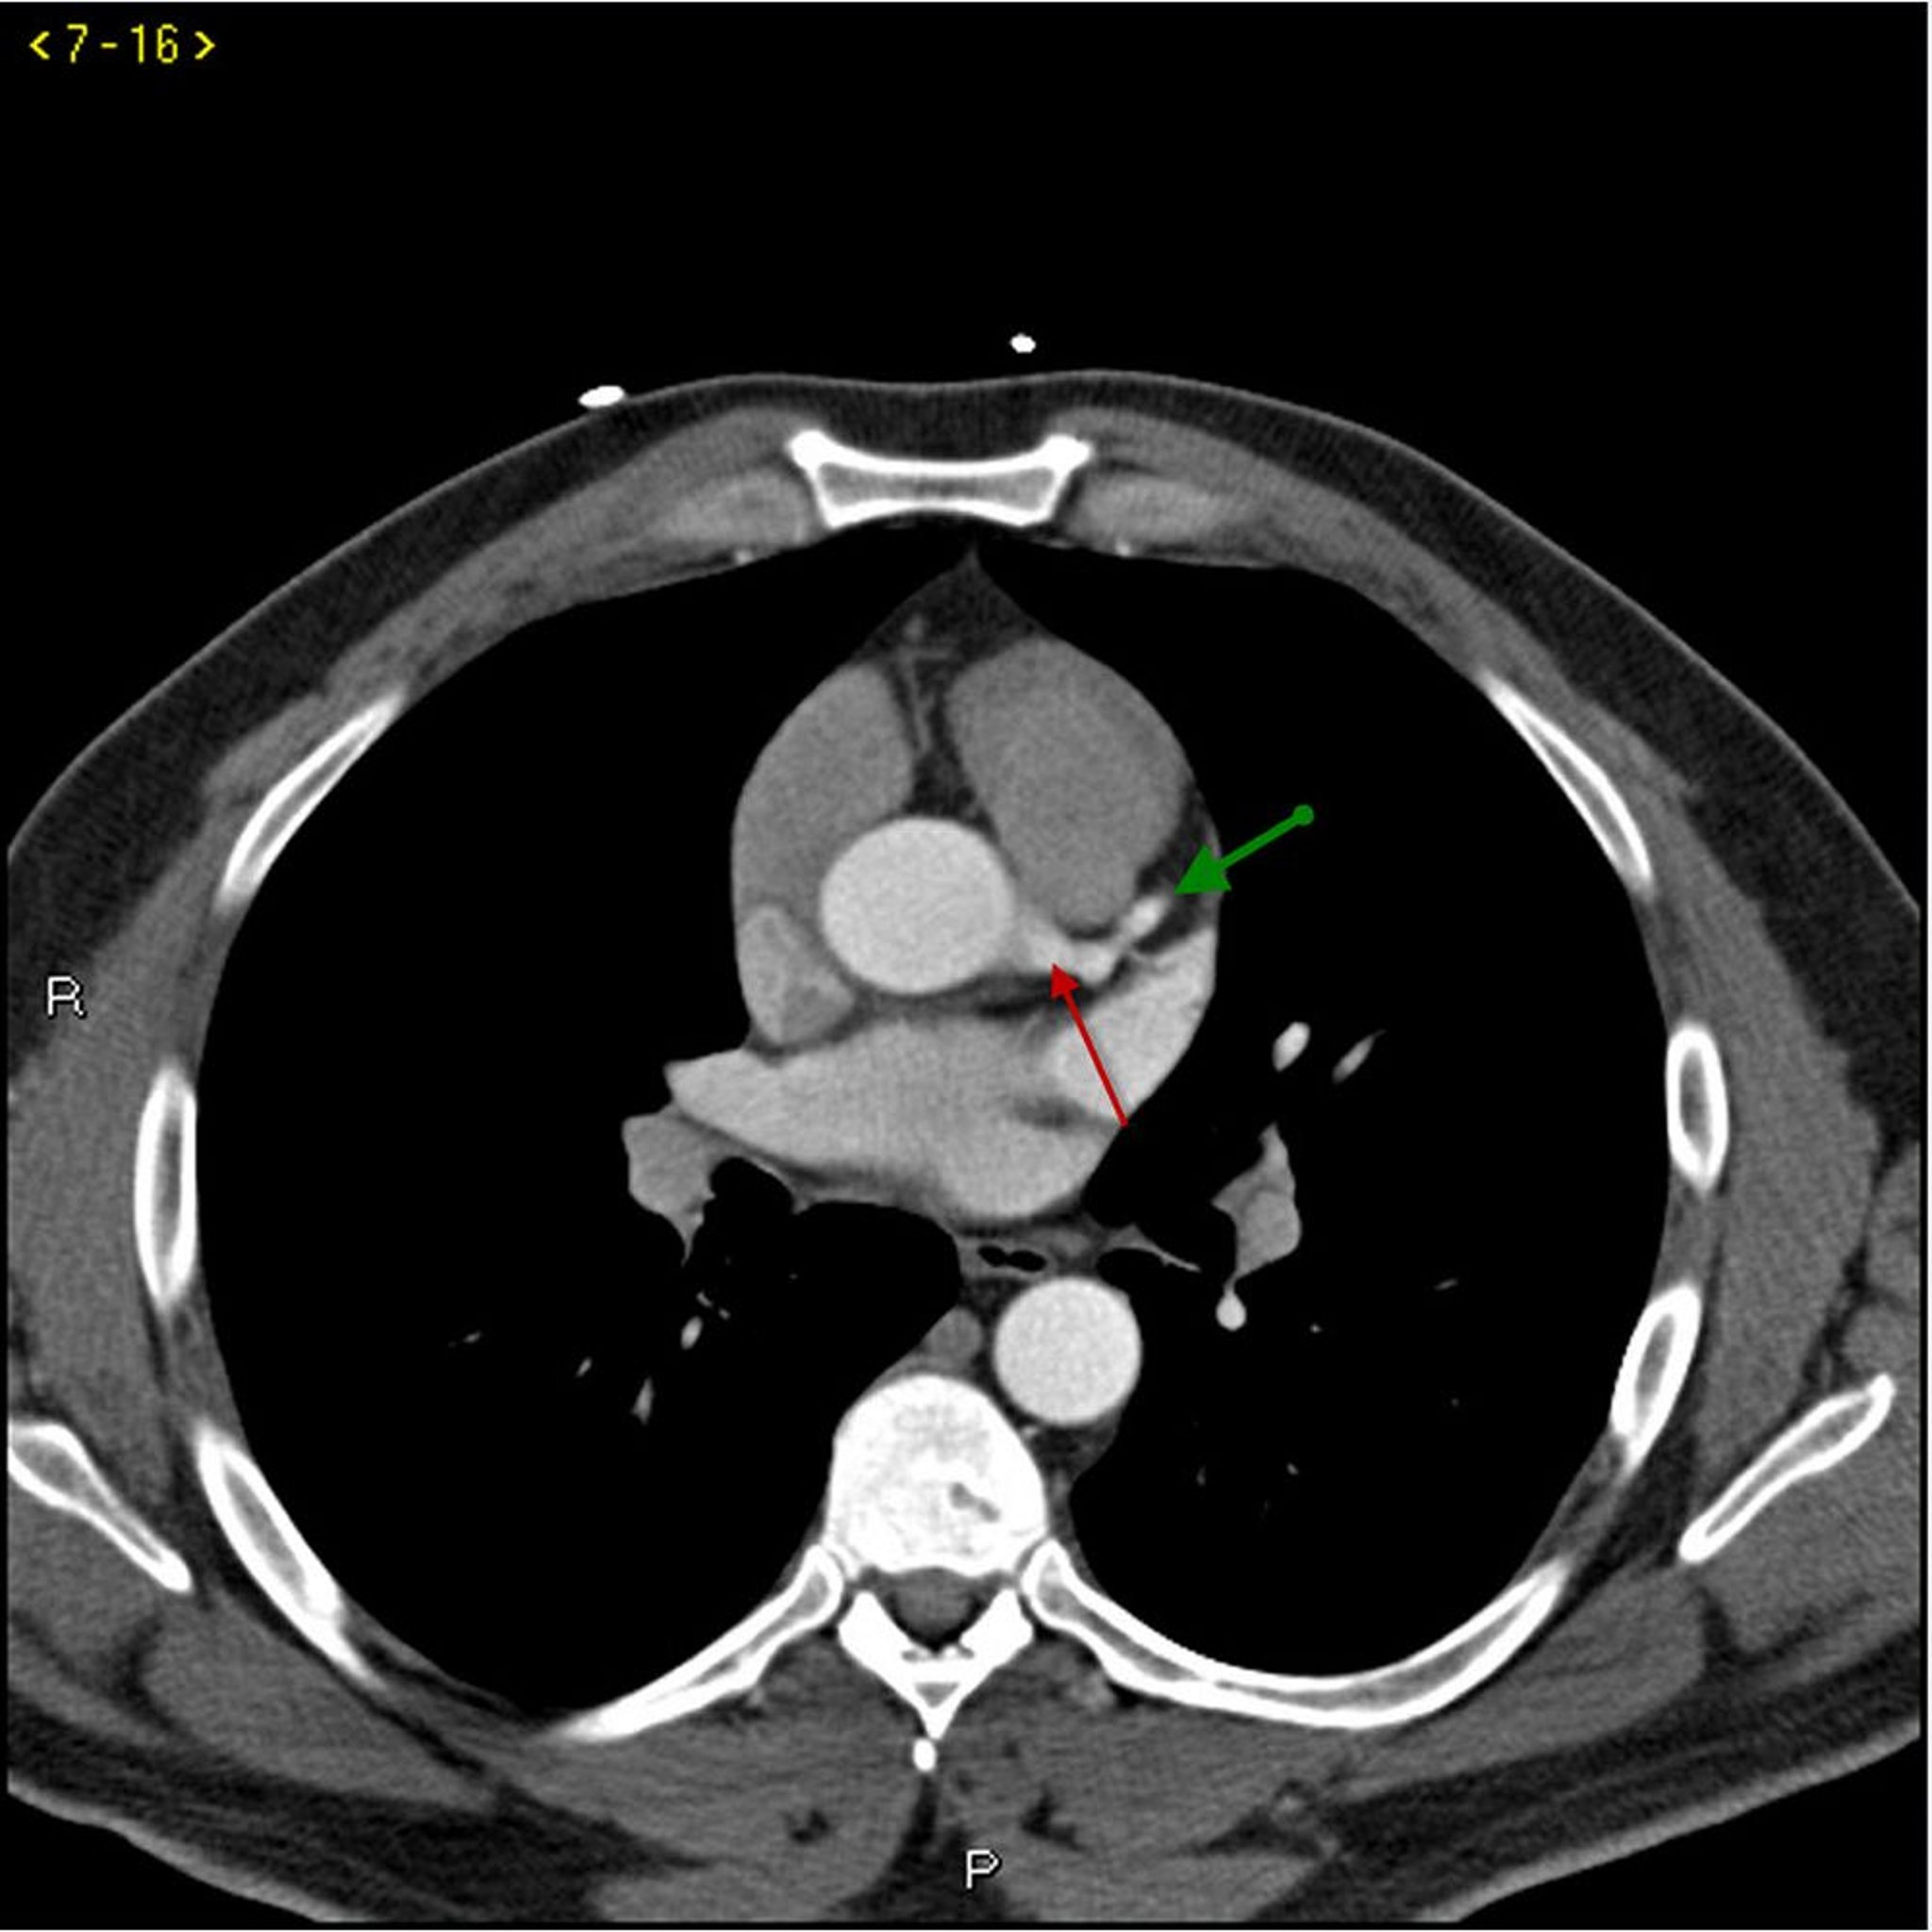

Contrast CT Showing Normal Coronary Arteries – Slide 1

This contrast CT shows normal coronary arteries. The left main is indicated by the red arrow. The left anterior descending and left circumflex arteries are indicated by the green and blue arrows respectively and the right coronary artery is indicated by the purple arrow.